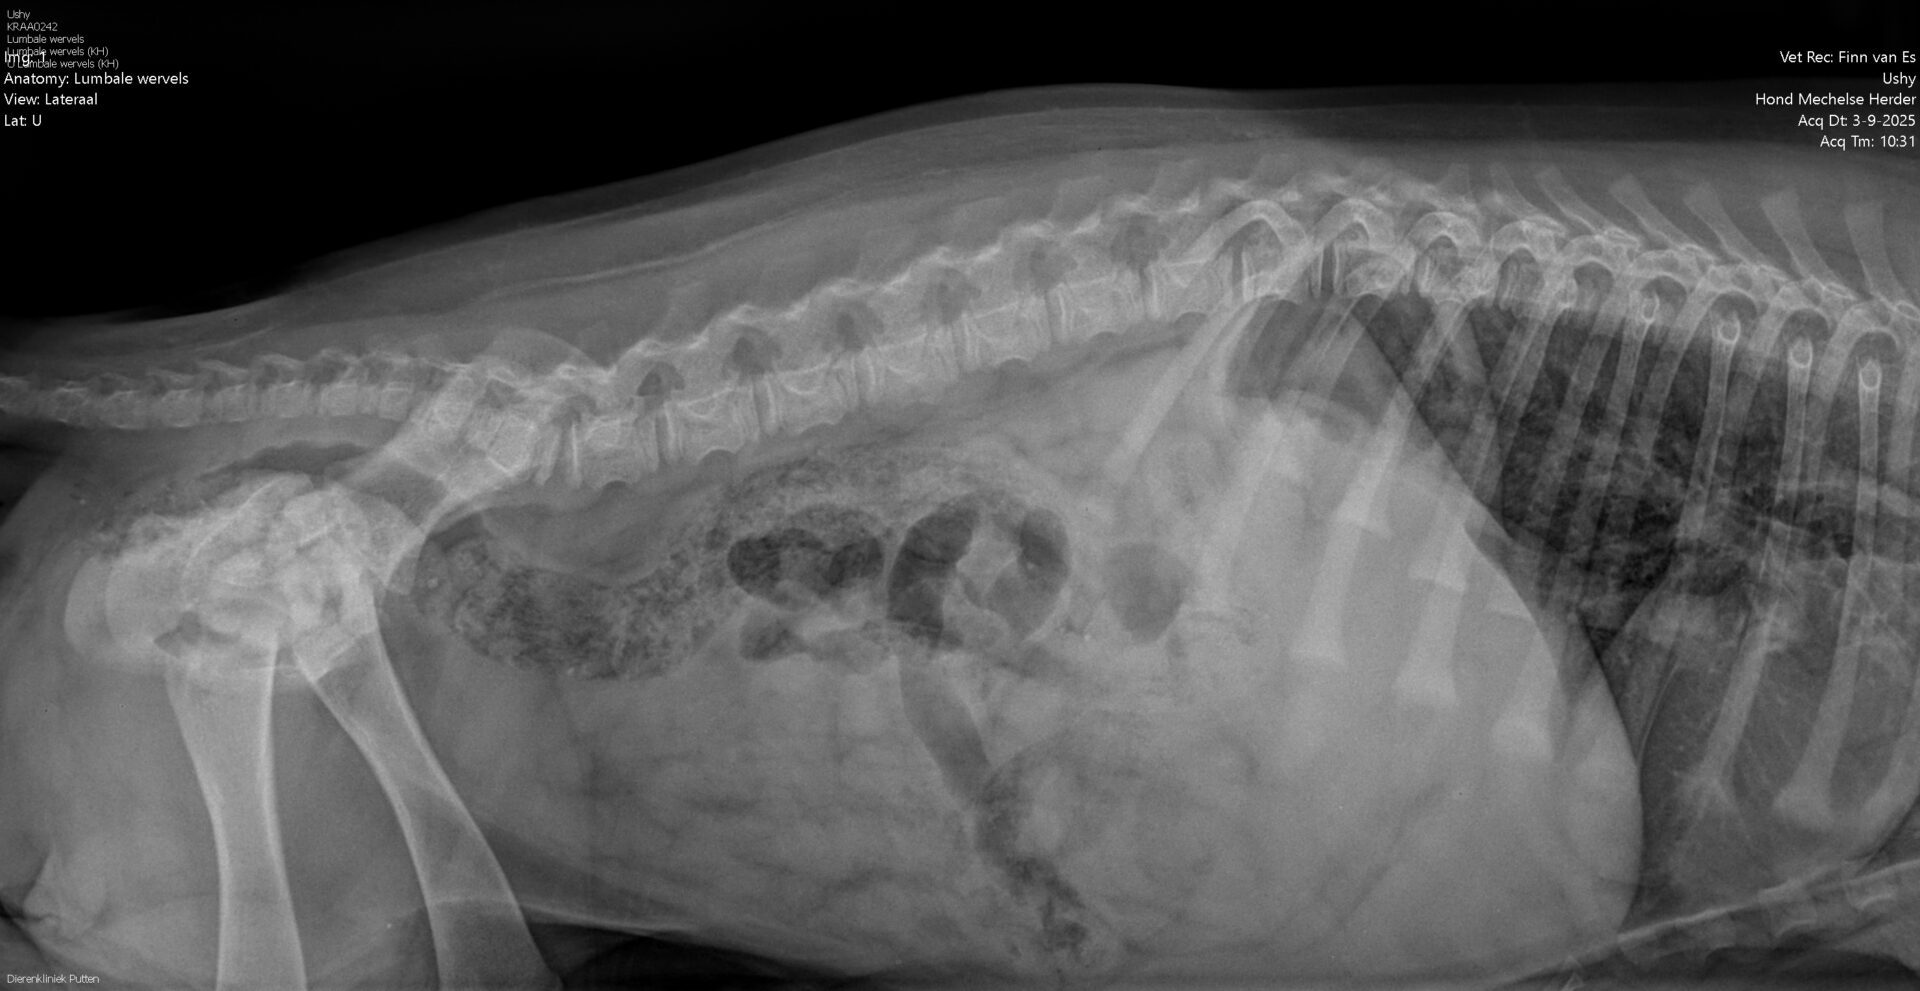

HD:

ED:

rug: 100%

Spondylose: vrij